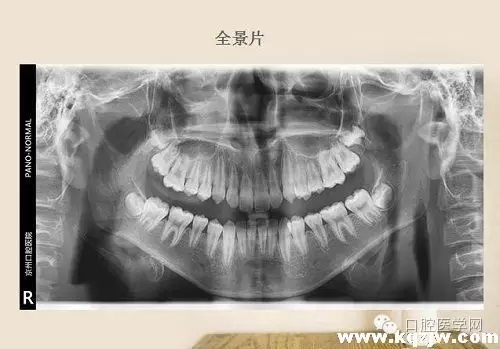

高角骨性三類(lèi)錯(cuò)頜一例